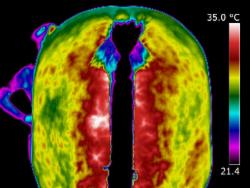

| MUSCLE INJURY | A very valuable use of thermography is in detecting muscle injury. It locates the area of inflammation associated with a muscle or muscle group. It can also show an area of atrophy before it becomes apparent clinically. Atrophy is seen as an area of consistent decrease in circulation when compared to the opposite side. Thermography allows us to see the specific location of strained or torn muscles. It can also help to assess the effects that have been placed on the musculo-skeletal system after extreme exertion and the extent of damage, or secondary damage, after a fall or accident. | | |

| | | When scanning initially, images of the whole horse must be assessed. If a muscle or muscle group shows a raised thermal pattern is the muscle damaged and inflamed or do these muscles simply have increased blood flow because they are working harder to compensate for injury or damage elsewhere? Only a well-trained, experienced thermographer is able to interpret the images.

When inflammation occurs in heavily muscled areas an intense thermal pattern will be evident over the affected area. If oedema and swelling occur over the strained muscle area, the surface temperature may actually become cooler due to subcutaneous fluid accumulation. Both types of images indicate an injury has occurred and careful observations are necessary to detect these differences.